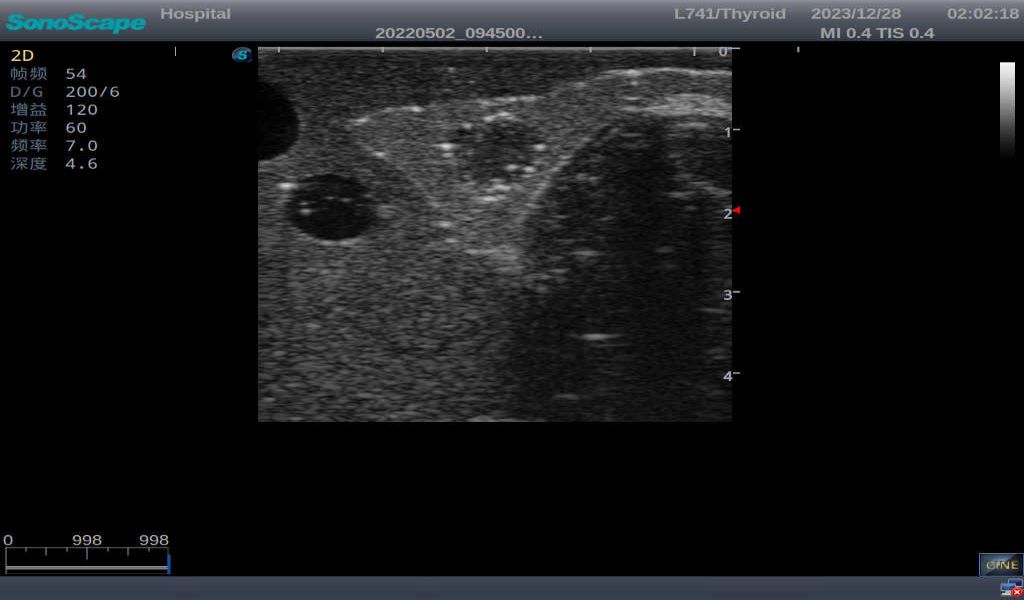

3) It comes with four (4) thyroid modules and can show five (5) ultrasonic images: normal thyroid, thyroid adenoma, thyroid cancer, nodular goiter, thyroid cyst

Nodular goiter with irregular border and varying sizes of low echo, isoechoic, or high echo nodules

Thyroid cyst, which fluid area, dark and echo-free area can be seen